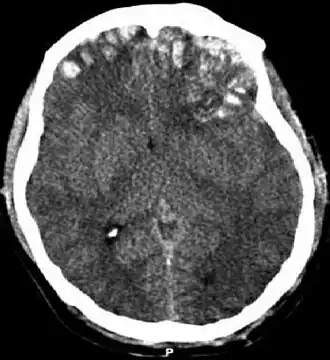

TAC mostrando contusiones cerebrales, hemorragia intracraneal entre los hemisferios, hematoma subdural y fracturas craneales[1] | ||

En el TCE grave o severo (ECG 3-8) el paciente tiene un estado comatoso, no puede abrir sus ojos, seguir órdenes y sufre de lesiones neurológicas significativas. Por lo general tiene una neuroimagen anormal, es decir, a la tomografía computarizada (TAC/TC) se observa fractura del cráneo o hemorragia intracraneal. Estos pacientes requieren ingreso a la unidad de cuidados intensivos (UCI) y la toma de medidas urgentes para el control de la vía aérea, ventilación mecánica, evaluación o intervención neuroquirúrgica y monitorización de la presión intracraneal (PIC). La recuperación es prolongada y generalmente incompleta. Un porcentaje significativo de pacientes con TCE grave no sobrevive más de un año.[7][5]

Los hematomas epidurales son los que se localizan entre la lámina interna craneal y la duramadre. Como se ha mencionado están asociados con fracturas de cráneo y ruptura de la arteria meníngea media o sus ramas. Son más comunes en las regiones parietales y temporales y son raros en las regiones frontales y occipitales. Se encuentran entre el 8% y 10% en pacientes con TCE grave. En la TAC, se ven como lesiones hiperdensas y biconvexas y debido a que no existe un espacio entre la duramadre y el hueso no suelen propagarse a menos que superen la adherencia de la duramadre. Estos hematomas son raros en infantes debido a que el cráneo es deformable lo que les confiere una protección. Además son raros en adultos mayores de 60 años debido a la adherencia débil de la duramadre al cráneo.[15]

Los hematomas subdurales se encuentran entre la cara interna de la duramadre y la superficie cerebral. Se encuentra entre el 20% y el 25% en pacientes con TCE grave. Son el resultado de hemorragia en las venas anastomóticas de la corteza cerebral superficial o ruptura de los senos venosos o sus tributarios y se asocian con daño en el tejido cerebral subyacente. Más específicamente se ha demostrado que un buen número de estos hematomas se deben a la ruptura de venas puente parasagitales.[31][32] Normalmente se expanden en la mayor parte de la convexidad cerebral pero no pueden propagarse al hemisferio contrario debido a la existencia de la hoz del cerebro. Los hematomas subdurales se clasifican en agudos, subagudos o crónicos dependiendo de la aparición y duración de estos y su aspecto característico en la TC:[15]

Contusiones

Las contusiones se encuentran en 20% al 25% de los pacientes con TCE grave. Son lesiones heterogéneas compuestas de zonas de hemorragia puntiforme, edema y necrosis que aparecen en las imágenes de TC como áreas de hiperdensidad puntiforme (hemorragias), con hipodensidad circundante (edema), suelen estar localizadas en la cara inferior del lóbulo frontal y la cara anterior del lóbulo temporal por su relación con el ala mayor del esfenoides. También se pueden encontrar en la superficie de impacto y en la superficie contraria a este, el llamado efecto golpe-contragolpe. Cuando estas evolucionan se parecen más a los hematomas intracerebrales y su ubicación depende el posible efecto de masa.